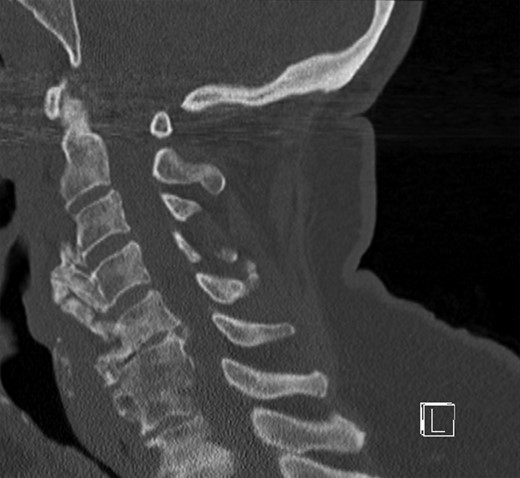

The X-ray and CT scan of the cervical spine revealed significant hyperostosis of the ventral cervical spine segments C3–C7. Hyperostosis was most extensive at segments C3–C5 causing stenosis of the pharyngeal lumen at the level of the larynx (Fig. 1). Due to accompanying joint pain, additional radiological examinations were performed. CT of the right shoulder showed extensive osseous proliferation of the medial humeral head reducing the articular space of the glenohumeral joint, as well as calcification of the rotator cuff (Fig. 2). In the left ankle, the CT scan revealed ossification of the deltoid ligament, and Kellgren grade 4 arthrosis of the tibiotalar and talocalcaneal joints (Fig. 3).

CT of the cervical spine in a sagittal view. Osteophytes of the ventral cervical spine segments C3–C5 protrude towards the oesophageal lumen.